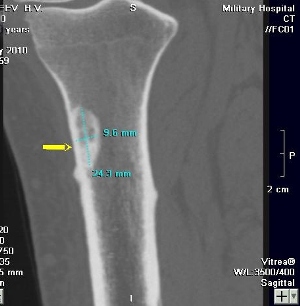

При рентгенологическом исследовании определяется крупный очаг до 20 см в диаметре, выходящий за пределы кости, но отграниченный надкостницей. Также определяются полости и разрушение костной ткани.

Диагноз основывается на клинических данных, рентгенологическом исследовании. Для уточнения характера новообразования проводят УЗИ, КТ, МРТ, ангиографию, пункционную трепанобиопсию пораженного участка, цитологический анализ внутриполостной жидкости.